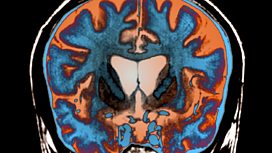

![]() - We discuss treatment that could have positive repercussions for other brain illnesses